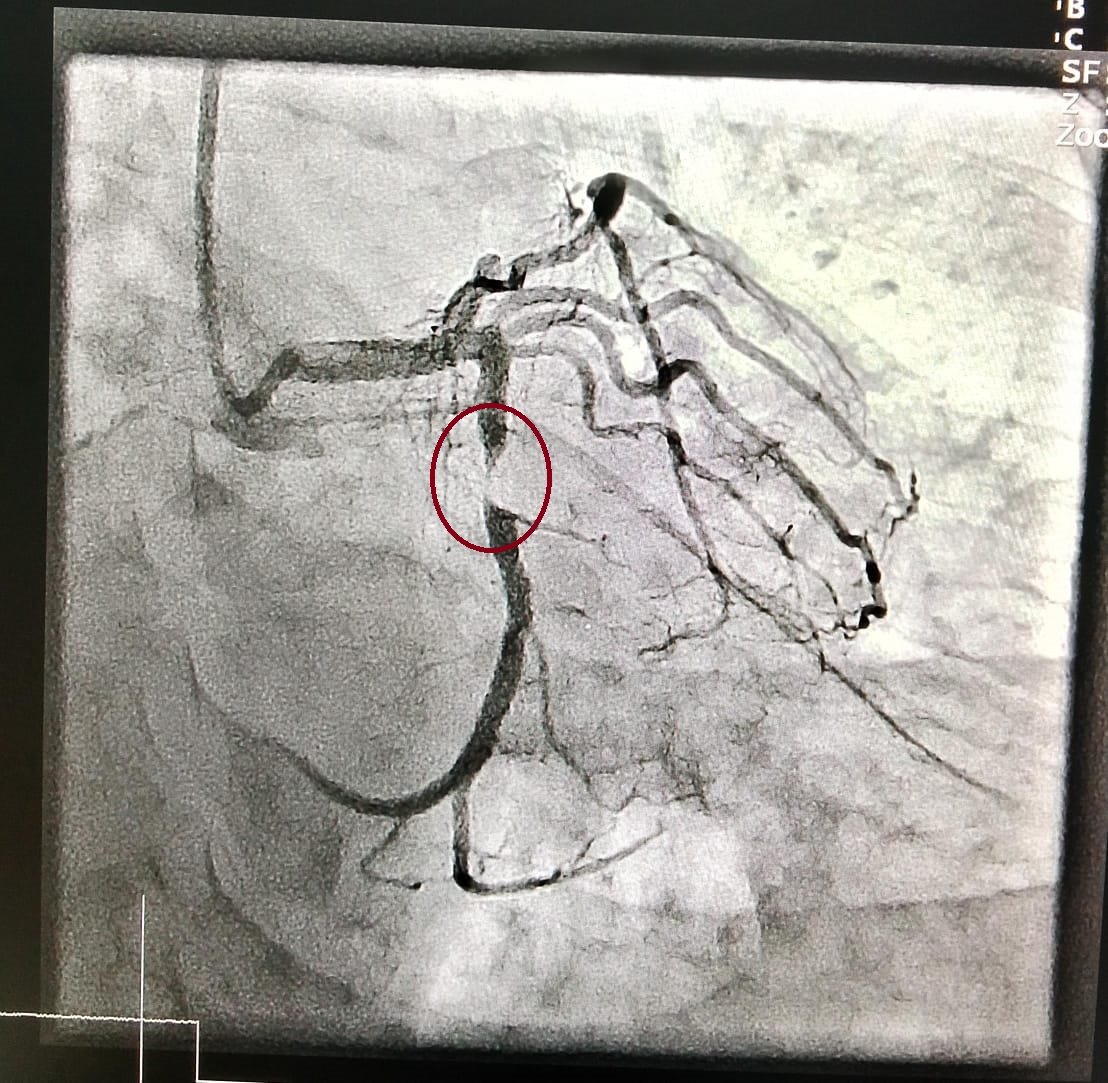

Treatment of blockages in the coronary arteries using angioplasty.

Dr. Masood Ahmed — with 33 years of experience in interventional cardiology — offers advanced angiography and angioplasty services for patients seeking alternatives to cardiac bypass surgery.

Cardiac procedures focus on diagnosing and treating heart-related conditions such as blocked arteries and irregular heart rhythms. Interventional procedures involve minimally invasive techniques to treat diseases in blood vessels, including legs, kidneys, neck, and brain, using imaging guidance instead of surgery.

In many cases, yes. Dr. Masood specializes in treating complex coronary and vascular conditions with angioplasty and stenting, often helping patients avoid open-heart surgery (CABG) or limb amputation.